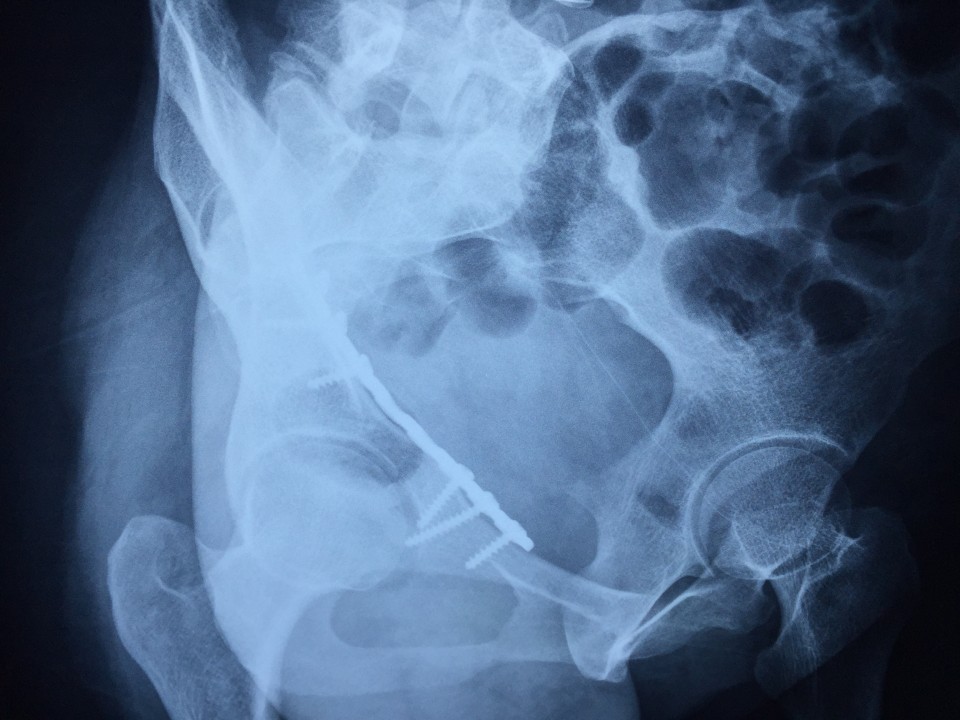

近日,我院创伤骨科七东利用改良Stoppa经腹白线旁入路成功治疗一例髋臼骨折患者。该患者女性,27岁,骨盆车祸伤。术前检查诊断为右侧髋臼骨折(AO分型为A3型)。该患者有剖宫产病史,腹部组织粘黏严重,手术难度较大。经过科室专家多次会诊,刘德宝主任制定详细手术方案,决定术中采用改良Stoppa入路,以减少手术创伤的影响。最终该手术顺利完成,历时一小时余,术中出血仅200ml,术后患者恢复良好。 采用改良Stoppa入路治疗髋臼骨折为安徽省首例,标志着我院创伤骨科进一步迈入创伤省内领先,国内先进的水平。

传统的对于髋臼前壁骨折的治疗方式主要为髂腹股沟入路,此入路内有重要的神经、血管经过,操作费时,术中可能导致股神经、血管及股外侧皮神经、精索或圆韧带的损伤。且骨折需通过3个窗口显露,骨折区域显露有限。针对髂腹股沟入路的缺点,我们使用改良Stoppa入路弥补了髂腹股沟入路的不足,它采用腹白线旁入路,推开腹膜内脏器,腹膜外达到真骨盆缘,一个窗口获得骨盆术野,可很好显露骨盆环。它有以下优点:此入路有宽阔的视野,并能直视骨盆缘,故可有效处理“死亡冠”,减少出血的发生;钢板塑形简单,钢板置入区域真骨盆内缘平坦,只需在一个平面预弯即可,并不需扭转钢板;可双侧骨盆缘复位固定,对于双侧耻骨上支及髋臼前柱骨折可轻易达到;术后病人康复快,因患者经下腹正中入路,并未损伤到髋部周围各层肌肉组织,故患侧肢体术后康复较快。据悉,此项技术在国内仅少数医院开展,在省内尚属首例。